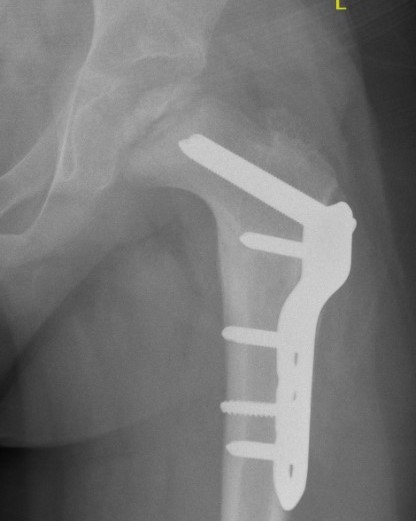

Technique

Synthes Pediatric Proximal Femur Offset Plate Technique PDF

Patient supine on radiolucent table

Lateral approach

- elevate vas lateralis +/- release proximally with L shaped release

- mark distal and proximal femur with drill holes to check rotation

- place wires up femoral neck short of physis

- use plate to mark osteotomy site

Osteotomy with microsagittal saw 1 cm below lesser tuberosity

- aim for 115o of varus

- avoid excessive varus < 100o to keep greater trochanter distal to femoral neck

- +/- adjust version

- apply plate and fix with screws